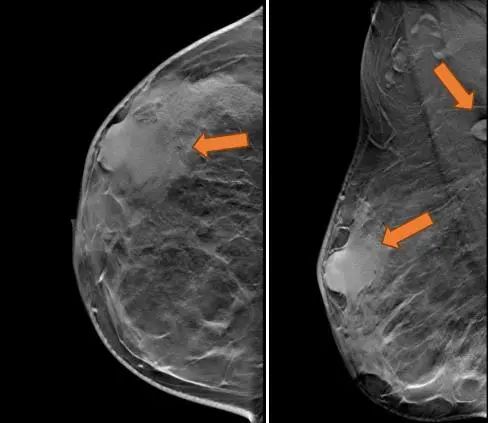

(3 cycle 后)2021.9.21 钼靶示:右乳外上象限不规则形肿块明显缩小,右腋窝淋巴结亦较前缩小。

图6. 钼靶

(3 cycle 后)2021.9.22 复查乳腺MRI示:右乳肿块较前减小14mm×9mm×18mm。

图7. 乳腺MRI